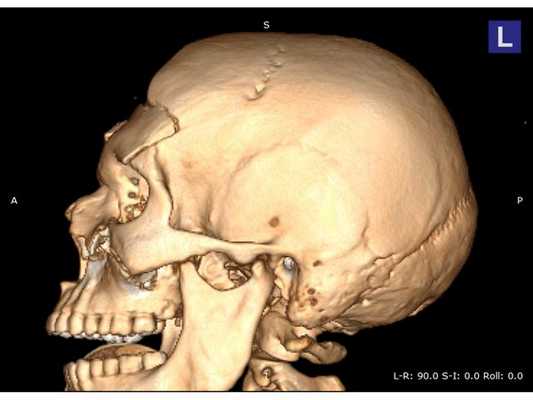

КТ головного мозга: оскольчатый вдавленный перелом лобной кости, линейный перелом ската затылочной кости, а также перелом лицевого отдела черепа III степени по Le Fort с остаточной деформацией стенок; множественные ушибы и отёк вещества головного мозга лобных долей; скопление крови в пазухах носа. КТ шейного и поясничного отделов позвоночника: травм и патологий нет. КТ грудной клетки и грудного отдела позвоночника: ушиб правого лёгкого. Офтальмологический осмотр: контузия правого глазного яблока тяжёлой степени, скопление крови между сетчаткой и пигментным эпителием левого глаза.

Сочетанная черепно-челюстно-лицевая травма. Открытая проникающая черепно-мозговая травма. Ушиб головного мозга тяжёлой степени с преимущественным поражением лобных долей и формированием очагов размозжения в полюсно-базальных отделах. Многооскольчатый вдавленный перелом лобной кости, переходящий на основание черепа. Перелом лицевого отдела черепа III степени по Le Fort с деформацией стенок правой глазницы. Ушиб правого глаза тяжёлой степени, субретинальное кровоизлияние левого глаза.